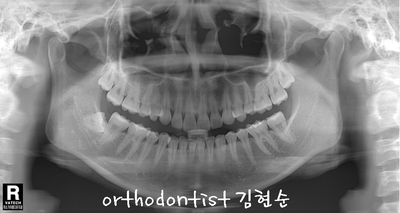

세라믹 치과 오시는 길 - 돌출 교정 - 교정 문의 환자 : 김 0 0 나이 : 24 세 F 교정 사유 : 치아 돌출 / 턱관절 호소 앞면 비대칭이 보입니다 웃을 때도 약간 삐뚤어 보입니다 입도 돌출된 모습을 확인할 수 있습니다 mi...

교정 문의 환자 : 김 0 0

나이 : 24 세 F

교정 사유 : 치아 돌출 / 턱관절 호소